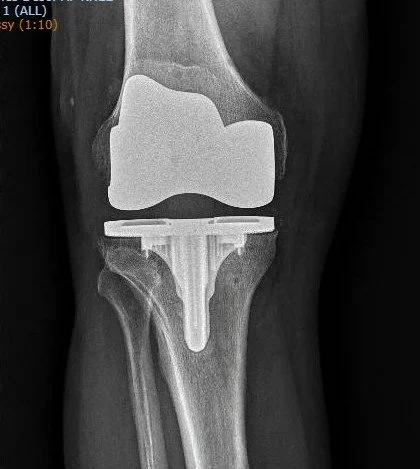

Robotic TKA

Dr. Ratner uses robotic technology for all of his knee replacements. Robotic total knee arthroplasty (TKA) is an advanced surgical technique that uses robotic technology to assist surgeons in performing knee replacement surgery with greater precision and personalization

Robotic TKA involves the use of a robotic arm or system guided by preoperative imaging (like CT scans) and real-time intraoperative data. The surgeon plans the procedure using 3D models of the patient’s knee, allowing for customized implant positioning and alignment tailored to the individual’s anatomy. During surgery, the robot provides feedback and assists with bone cuts, ensuring accuracy within millimeters, while the surgeon retains full control.

- Improved Precision and Accuracy - Robotic systems enhance the precision of bone cuts and implant placement, aligning the prosthetic components more accurately with the patient’s unique anatomy. Traditional TKA relies heavily on manual tools and surgeon experience, which can lead to slight variations.